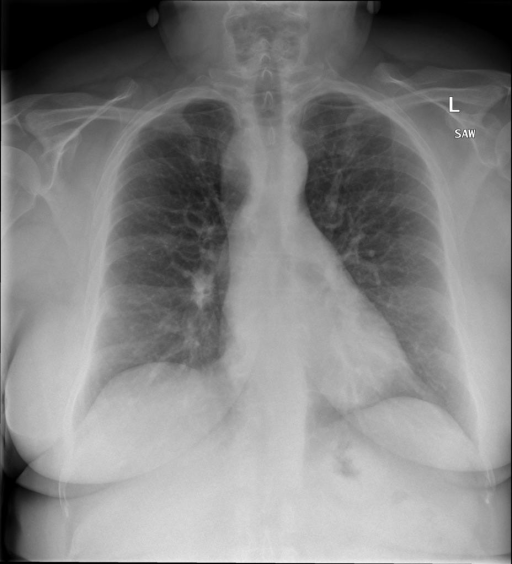

- (1)准备[诊疗报告(中文)](./data/Xray/openi-zh.json)和[X光影像](https://pan.baidu.com/s/13GBsDMKf6xBZBSHpoWH_EA?pwd=k9sh)在`data/Xray`文件夹下; - (2)开始训练: ```bash # 设置CUDA变量,主要是为了解决有时候直接训练而出现无法正确加载到显卡问题 export CUDA_VISIBLE_DEVICES=0,1,2,3 # 开始训练 bash finetune_XrayGLM.sh ``` 这里的复现过程非常简单,主要是很多过程我们都为大家准备好了,大家可以随时复现一个自己的`XrayGLM`。 ### 4.模型训练(通用) ## 效果展示 影像诊断: |X光影像|诊疗报告(医生)|XrayGLM| |:-|:-|:-| |![](./data/Xray/2_1.png)|根据X射线图像,心脏大小正常,肺部看起来很清晰。已经排除了肺炎、积液、水肿、气胸、腺病、结节或肿块的存在。该发现表明一切正常。换句话说,总体印象是胸部正常。|X光片显示,心脏大小正常。肺部没有气胸或胸腔积液的证据。骨骼结构看起来没有任何异常。总的来说,X光片表明没有发现急性心肺疾病的迹象。| |![](./data/Xray/2882_1.png)|X光图片显示没有扭曲的区域、可疑的骨质不透明度或胸腺积液。心脏大小轻微增大,但非常稳定。此外,没有气胸的证据,肺野也正常。总体来说,X光片显示没有急性心脏异常,但要注意轻微的心脏扩大。|X光片显示,心脏大小正常。肺部和纵隔轮廓清晰,没有气胸或胸腔积液的证据。骨骼结构完整,没有任何急性异常。| |![](./data/Xray/2577_1.png)|心影形态在正常范围内。没有急性骨质异常。有可能出现没有明显的吸水或肺实质状况的线索。没有大面积积液或气胸。有可能怀疑其有误吸或肺实质问题。为了确诊和治疗,可能需要进行适当的影像学随访。|心脏大小正常,肺部和纵隔轮廓清晰。没有急性异常或活动受限的证据。没有任何明显的气胸、胸腔积液或肺不张的迹象。此外,也没有发现任何局灶性骨质异常或其他急性疾病。| 多轮对话: |X光影像|诊疗报告(医生)| |:-|:-| |![](./data/Xray/861_1.png)|右侧主动脉突出观察到。心脏大小正常。胸部未发现明显的肺气肿、胸膜积液或可疑的肺部病变。报告指出已知右侧主动脉情况正常。| ```bash >> X光影像路径:./data/Xray/861_1.png >> 用户:这是一张什么图? >> XrayGLM:这张图片显示的是一张肺部检查的X光片。 >> 用户:请描述这张胸部X光片的诊断结果 >> XrayGLM:心脏大小正常,肺部清晰。没有急性心肺疾病的证据。 >> 用户:是否存在肺气肿? >> XrayGLM:没有肺气肿。心脏大小正常,肺部清晰。没有发现急性心肺疾病的证据。 >> 用户:平时饮食该注意什么? >> XrayGLM:饮食应该健康,均衡。建议增加蛋白质的摄入量,因为蛋白质有助于维持肌肉和骨骼的健康。多食用蔬菜、水果、全谷物以及健康的脂肪来源如橄榄油、鱼类等可以帮助获得足够的维生素和矿物质。此外,避免过度饮酒或吸烟,这些习惯可能会对心脏健康产生负面影响。 ``` ## 未来展望 1. 模型的能力更多来源于数据的支持,`OpenI-zh`作为微调数据集,其数据量足以支持研究,在更广泛的任务和性能表现上,我们认为**在大规模数据集上预训练并在高质量少量数据集上微调是一种可行的方案**; 2. 普遍意义的理解上,视觉多模态模型=视觉模型+语言模型。除了需要关注视觉模型信息与语言模型输出的搭配外,还需要**额外关注到语言模型的加强,在人机的对话中,尤其是医疗语言模型的问答上,除了专业的医疗问题回答,带有人文情怀的有温度的回答更应该是我们追寻的目标**。 ## 项目致谢 1. [VisualGLM-6B](https://github.com/THUDM/VisualGLM-6B)为我们提供了基础的代码参考和实现; 2. [MiniGPT-4](https://github.com/Vision-CAIR/MiniGPT-4)为我们这个项目提供了研发思路; 3. ChatGPT生成了高质量的中文版X光检查报告以支持XrayGLM训练; 4. [gpt_academic](https://github.com/binary-husky/gpt_academic)为文档翻译提供了多线程加速; 5. [MedCLIP](https://github.com/RyanWangZf/MedCLIP) 、[BLIP2](https://huggingface.co/docs/transformers/main/model_doc/blip-2) 、[XrayGPT](https://github.com/mbzuai-oryx/XrayGPT) 等工作也有重大的参考意义; ![](./assets/images/mpu.png) 这项工作由[澳门理工大学应用科学学院](https://www.mpu.edu.mo/esca/zh/index.php)硕士生[王荣胜](https://github.com/WangRongsheng) 、[段耀菲](https://github.com/IsBaSO4) 、[李俊蓉](https://github.com/lijunrong0815)完成,指导老师为檀韬副教授、[彭祥佑](http://www.patrickpang.net/)老师。 *特别鸣谢:[USTC-PhD Yongle Luo](https://github.com/kaixindelele) 提供了有3000美金的OpenAI账号,帮助我们完成大量的X光报告翻译工作 ## 免责声明 本项目相关资源仅供学术研究之用,严禁用于商业用途。使用涉及第三方代码的部分时,请严格遵循相应的开源协议。模型生成的内容受模型计算、随机性和量化精度损失等因素影响,本项目无法对其准确性作出保证。即使本项目模型输出符合医学事实,也不能被用作实际医学诊断的依据。对于模型输出的任何内容,本项目不承担任何法律责任,亦不对因使用相关资源和输出结果而可能产生的任何损失承担责任。 ## 项目引用 如果你使用了本项目的模型,数据或者代码,请声明引用: ```bash @misc{wang2023XrayGLM, title={XrayGLM: The first Chinese Medical Multimodal Model that Chest Radiographs Summarization}, author={Rongsheng Wang, Yaofei Duan, Junrong Li, Patrick Pang and Tao Tan}, year={2023}, publisher = {GitHub}, journal = {GitHub repository}, howpublished = {\url{https://github.com/WangRongsheng/XrayGLM}}, } ``` ## 使用许可 此存储库遵循[CC BY-NC-SA](https://creativecommons.org/licenses/by-nc-sa/4.0/) ,请参阅许可条款。